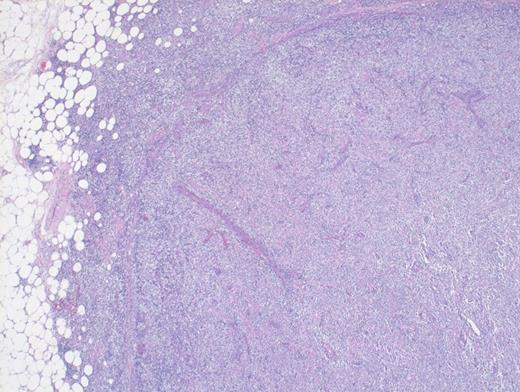

Hematoxylin and Eosin Stain Depicting Architectural Effacement by this Proliferation of Medium Sized Mononuclear Cells.

A 73-year-old woman with a history of autoimmune hepatitis presented with abdominal pain and fever. On further examination, the patient was noted to have hypergammaglobulinemia, elevated lactate dehydrogenase (LDH), and diffuse lymphadenopathy on imaging. An excisional biopsy of a superficial lymph node was performed. The images below are of a hematoxylin & eosin stain depicting architectural effacement by this proliferation of medium sized mononuclear cells (Figures A and B) containing numerous wisps of follicular dendritic cell meshworks (Figure C) and few scattered Epstein-Barr virus (EBV)+ cells (Figure D).

Angioimmunoblastic T-cell lymphoma (AITL) is histologically identified by T-cells having ample clear cytoplasm in a background of prominent vasculature and a mixed inflammatory microenvironment (plasma cells, histiocytes, and immunoblasts). The process effaces the typical nodal architecture with retraction of the peripheral cortical sinuses, in addition to numerous new follicular dendritic meshworks outside of the follicles in the perivenular regions. There are numerous associated reactive B-lineage immunoblasts in the background in addition to the neoplastic T-cells.1 This specific case was positive for CD3 and CD4 on the clear cells.